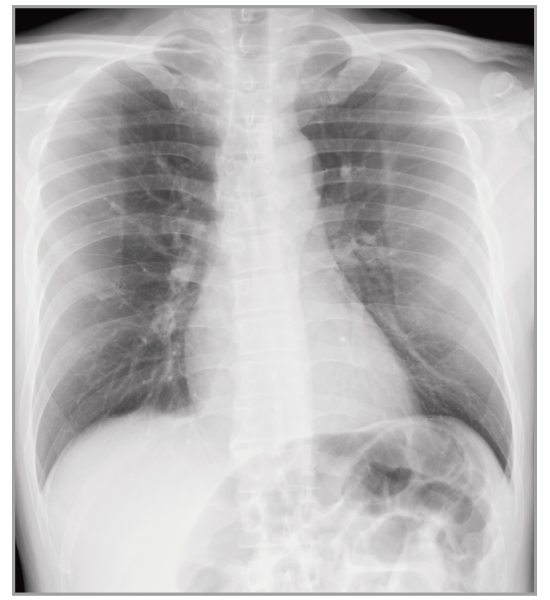

Multiple body parts supported

Abdomen

Cervical Spine

Thoracic Spine

Lumber Spine